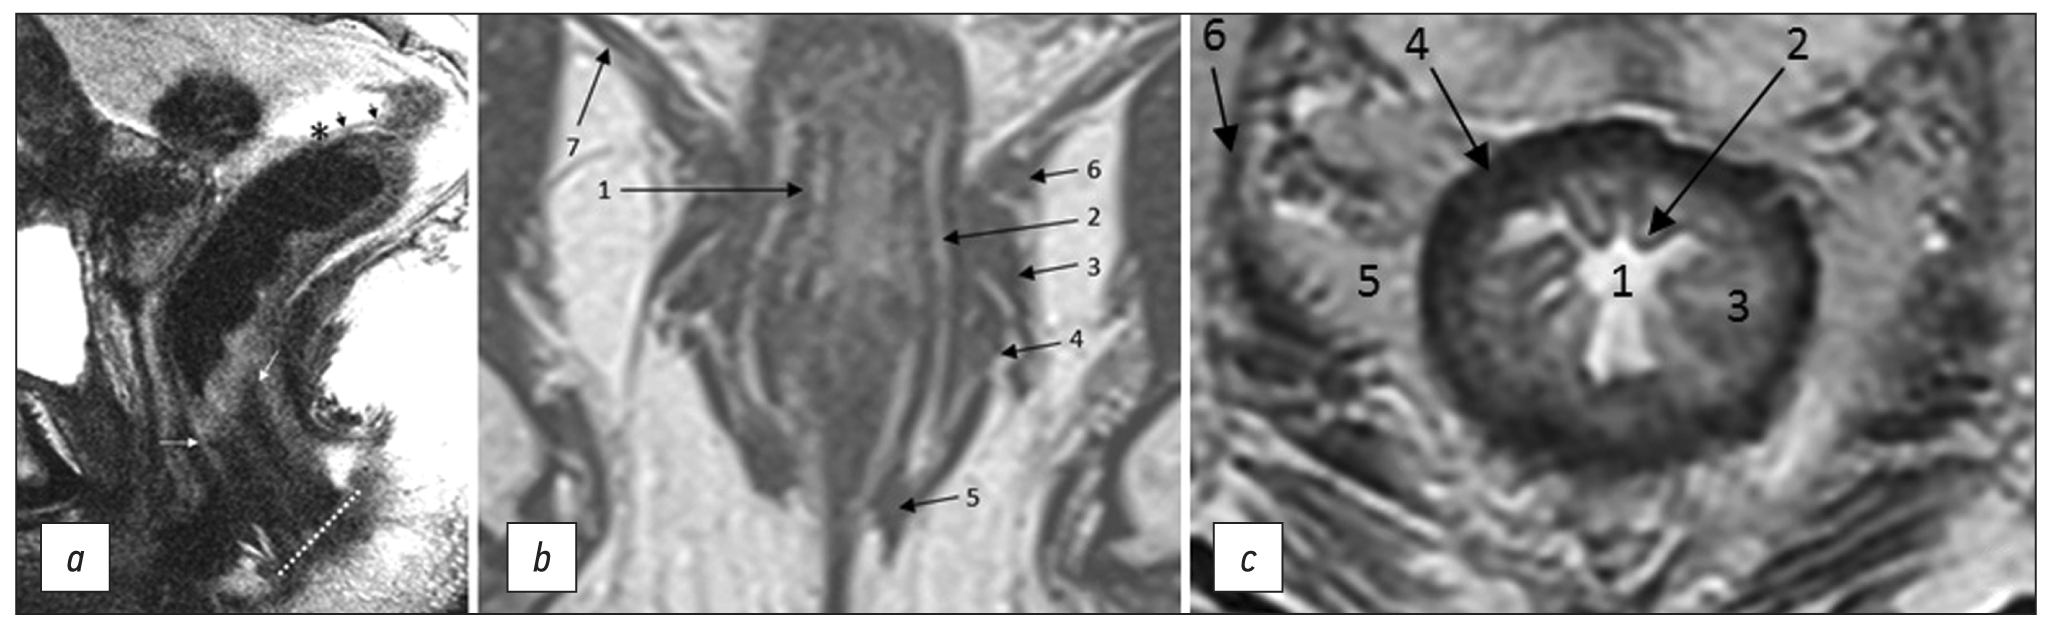

Conventional magnetic resonance imaging of peripheral nerves: MR-neurography

Abstract

Peripheral neuropathy is known to be one of the most common neurological disorders. Despite the great diagnostic value of electroneuromyography and ultrasound, addressing the diagnostics and differential diagnostics of peripheral nerve diseases of different origin could be challenging. In recent years, magnetic resonance tomography has been increasingly used for evaluating cases of suspected or established peripheral neuropathy with excellent results.

This manuscript mainly deals with the advantages and limitations of the aforementioned diagnostic instruments, technical considerations according to different anatomy of peripheral nerves, along with state-of-the-art technical decisions, frequently used magnetic resonance imaging sequences and their diagnostic value based on own observation, and recommendations for contrast enhancement use and different methods of fat suppression.

Currently, there is practically no standardized description of normal magnetic resonance imaging features of peripheral nerves, as well as their changes in different diseases. The evaluation of images is mainly based on the radiologist experience, which obviously decreases method’s diagnostic value. Studies of large numbers involving healthy volunteers and patients with peripheral neuropathies of different origin are required to address this issue.